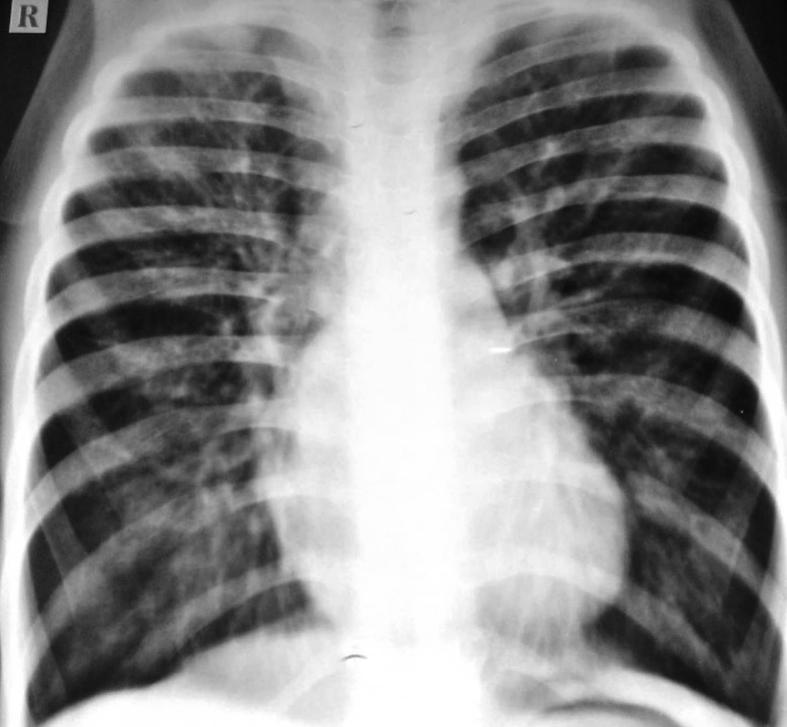

Allergic bronchopulmonary aspergillosis (ABPA) is a complex hypersensitivity reaction in patients with asthma or cystic fibrosis (CF), which is associated with bronchi colonized by the fungus Aspergillus species, most often Aspergillus fumigatus. ABPA is an important consideration for asthmatics that do not respond to asthma management or with recurrent chest infections and deteriorating lung function in children with cystic fibrosis. We present two cases of non CF bronchiectasis associated with ABPA who presented to our hospital with recurrent hospitalisations of undiagnosed aetiology.

变应性支气管肺曲霉病(ABPA)是哮喘或囊性纤维化(CF)患者发生的一种复杂的超敏反应,与曲霉菌属真菌(最常见的是烟曲霉)定植于支气管有关。ABPA是那些哮喘治疗无反应或反复出现肺部感染且肺功能恶化的囊性纤维化儿童哮喘患者需要重点考虑的疾病。我们报告两例与ABPA相关的非CF支气管扩张症患者,他们因病因不明反复住院而前来我院就诊。